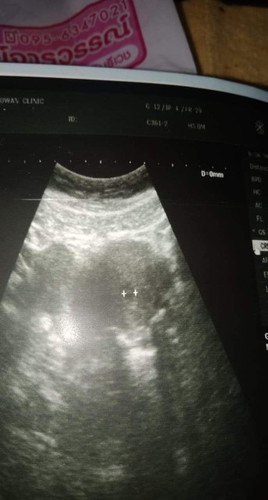

ท้อง5สัปดาห์

สอบถามหน่อยค่าท้องกี่สัปดาห์ถึงจะเห็นตัวเด็กค่ะพอดีไปอัลตร้าซาวด์ ยังไม่เห็นตัวเด็กค่ะ กลัวว่าจะเป็นท้องลม

ซาวด์ทางหน้าท้องหรือช่องคลอดคะแม่ ถ้าทางหน้าท้อง ถ้าตัวอ่อนยังเล็กมากๆ หรือเป็นคนหน้าท้องหนา อาจจะยังไม่เห็นค่ะแม่ ทางช่องคลอดจะพอมีลุ้นมากกว่าค่ะ ทั้งนี้เป็นไปได้ว่า อายุครรภ์อาจจะน้อยกว่าที่นับ เพราะไข่อาจจะตกช้ากว่ากำหนด ตัวอ่อนยังเล็กมากอยู่ จึงยังไม่พบ ก็เป็นได้ค่ะแม่ ทานโฟลิคทุกวัน พักผ่อนเยอะๆ นะคะ ซาวด์ครั้งหน้าอาจจะได้เจอกันแล้วจ้า